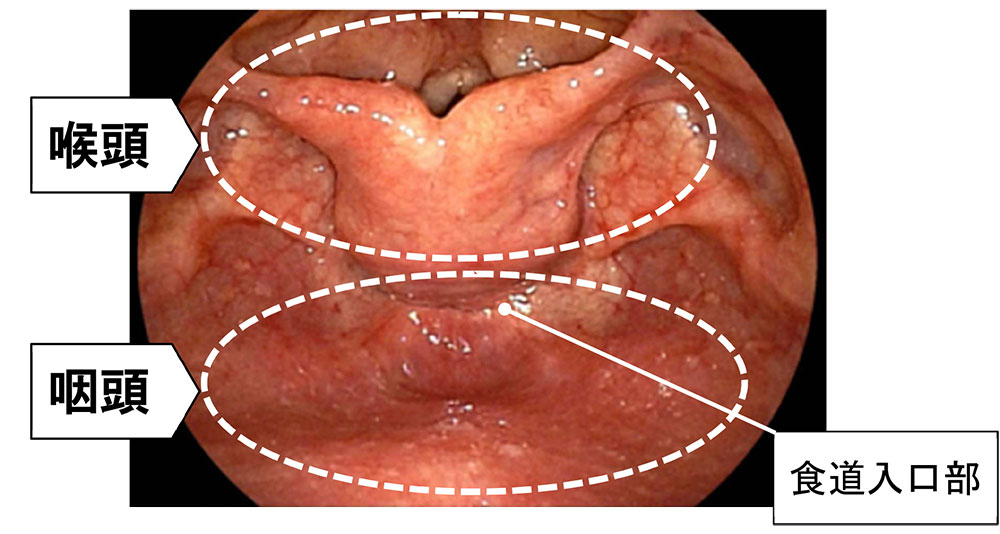

人間は常に呼吸をしています。そのため、ノドを内視鏡で見てみると、通常は図のように

喉喉頭が広く展開し、声帯が大きく開いて、気管に空気が入りやすいようになっています。

一方、食べ物を飲み込むときは、図のように喉頭全体がシャッターのように図の上側にあがり、咽頭が広く展開され、食道に食べ物が流れ込むようになります。

このとき、声帯は閉鎖して気管の蓋になって、食べ物が気管に入り誤嚥するようなことがないようにしてくれます。

しかし、実際には頸部食道がんで手術を受けられた患者様の約3分の2で喉頭摘出手術が行われています。これは、食道入口部付近は図のように喉頭や気管、椎体といった硬い構造物に囲まれた狭い領域であるため、がん病巣を確実に取り残しなく摘出し、新たな食べ物の通り道を作成する(消化管再建)手術手技の難易度が高いことが一つの原因です。

図は喉頭回転法を用いて手術を行った患者様の手術後の内視鏡の写真です。

この患者様はがん病巣が一部下咽喉にまで広がっていましたが、喉頭を温存しながら頸部食道と下咽喉の一部を摘出し、下咽喉の高さで消化管吻合を行いました。手術後も問題なく発声が可能でした。